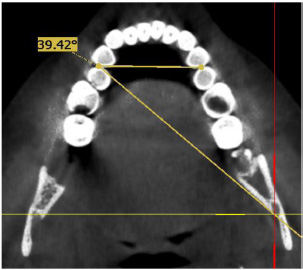

- MF–CLP angle: The coronal view was used to adjust the sagittal plane to the inferior border of MF; then, the axial plane was adjusted to match the level of and come into contact with the mandibular premolars. Afterwards, from the axial view, a straight line was drawn between the contact areas of premolars, and another line from the CLP contact area to the MF was created (Fig. 1).

Axial view demonstrating CLP angle.